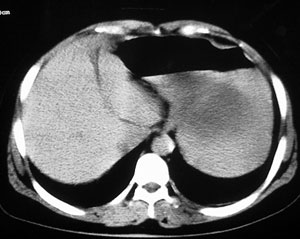

女44腹部不适

接着ct4478平扫

胰腺体尾部囊实性占位,有分隔.内无脂肪及钙化等组织.胰腺囊腺瘤.

这个要问下病史,如无胰腺炎病史首先考虑胰腺体尾部的粘液囊腺瘤,此瘤太大,有分叶和实性成份要考虑恶性或潜在恶性可能,后两幅主动脉左旁结节状强化影止于左肾静脉,考虑双下腔静脉,请结合往下的片

胰腺体尾部囊实性占位,境界清晰,内有间隔呈多房性,周围无炎性改变,考虑胰腺囊腺瘤。